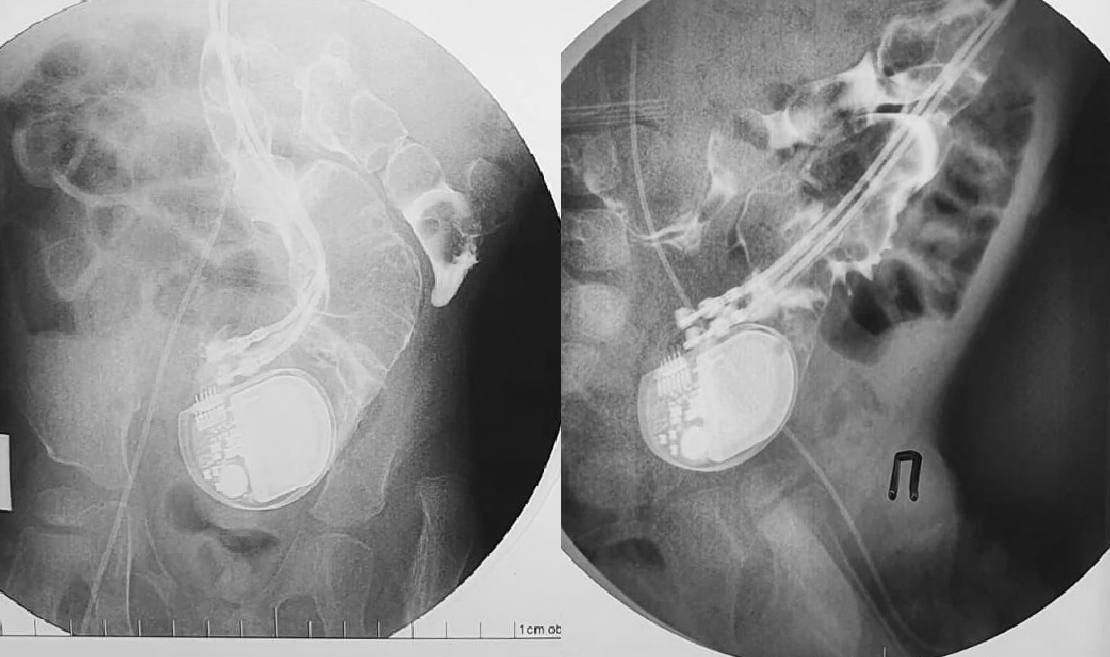

Новосибирские хирурги вытащили кардиостимулятор из кишечника ребёнка.

У малыша редкая аритмия, в возрасте двух дней ему поставили стимулятор — без него бы не выжил. Через три года мальчишка попал в барнаульскую больницу с температурой. Рентген показал, что работающий прибор переместился в кишечник и застрял там окончательно из-за электродов и проводки.

Бригада детских хирургов Новосибирской областной клинической больницы провела операцию. Устройство извлекли, а в грудь поставили новый аппарат. Через 10 дней мальчик отправился домой.